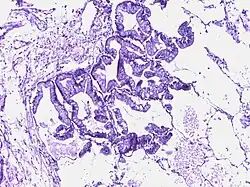

Bronchoalveolar carcinoma | Lepidic pattern of growth of tumor cells along the alveolar wall resembling butterfly sitting on fence. Normal alveoli is seen towards right side. | Category: Histopathology of bronchio-alveolar carcinoma | Bronchio-alveolar carcinoma |

![]() |